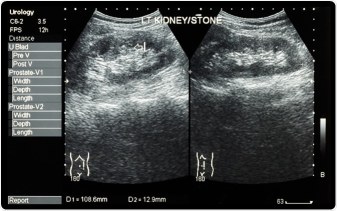

A las piedras se les hace un nudo

en la garganta muda del futuro

y les crecen hombrecitos angulosos

en la pulpa de los riñones.

Excepto mi corteza y mis riñones.